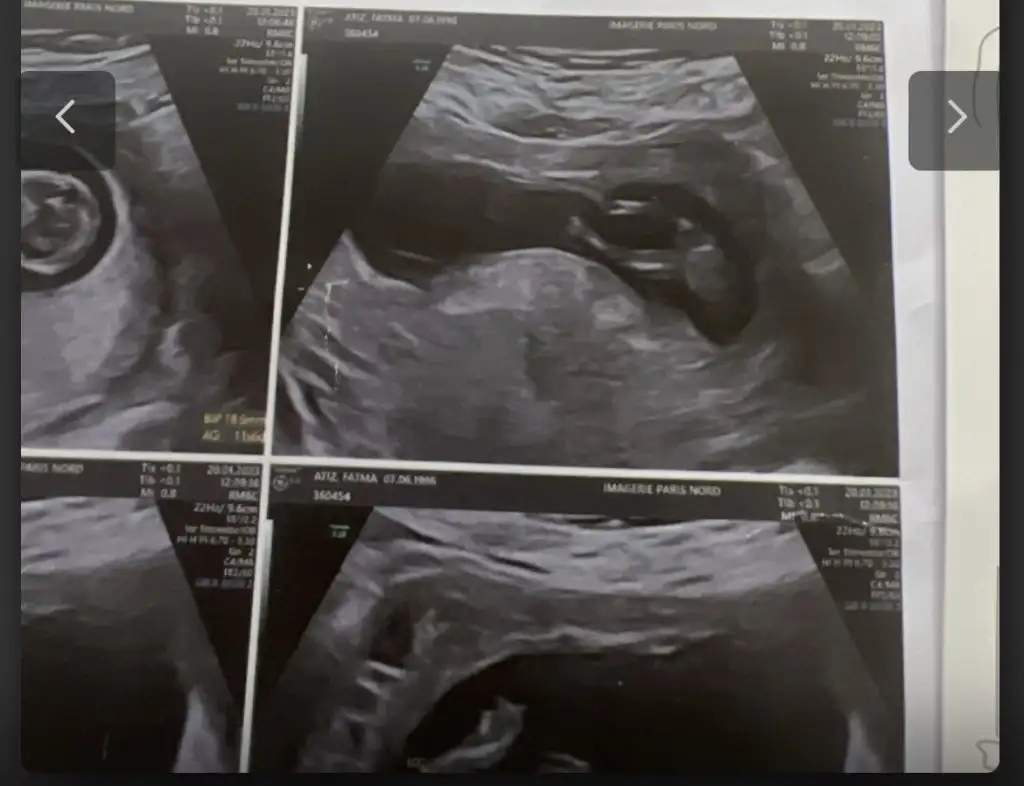

Merhaba arkadaşlar bu benim ilk hamileliğim o yüzden çok bilgim yok, bugün 12+4 de ikili ultrason yapıldı doktor cinsiyeti ne hissediyorsun dedi açıkçası içime herhangi bir şey doğmuyor yani kız yada erkek diye. Doktorum benim içime kız doğuyor haberin olsun dedi. Çok sevindim ama sonrasında kime söylesem hemen moda girme o sadece bi tahmin daha belli olmaz diyorlar. Erkek bebek kendini erken gösterir kızı 16. Haftaya kadar zor görüyorlar nasıl hemen söylemiş falan dedi yani şimdi kız dedi ama sonradan yanılma gibi bir payı var mı ? Çok mu erken cinsiyet için. Üstelik doktor çok sevindiğimi görünce yine de herkese söyleyip pembe şeyler alma hemen netleşsin , bana da bu zamanlar kız demişlerdi şimdi oğlum var dedi , ama 3 kez de üstüne basarak kız gibi görüyorum dedi. Açıkçası herkesin yorum yapması biraz böyle kafamı karıştırdı. Kız yada erkek asla farketmez sonuçta kızımda yok oğlumda ama insan ilk gebelik heyecanıyla bilip herkese söylemek istiyor sanırımböyle öğrenip sonradan cinsiyet değişen doktoru yanılan var mı ? Eskiler de çokmuş bu durum ama şimdi cihazlar çok gelişmiş olma diye umuyorum. Bu Arada fotoğrafta yüklüyorum belki sizde bi tahminde bulunursunuz

Nubu tam net gorunmuyo kapatmis ama kafa yapisi kiza benziyo yuvarlak kiz olma ihtimali yuksekBu foto 11haftalik cnm

Nubu tam net gorunmuyo kapatmis ama kafa yapisi kiza benziyo yuvarlak kiz olma ihtimali yuksek

Doktor kiz oldugunu soylemis olmali bacak arasi bos cnku

Beklemekte fayda var bazi bebekler gostermiyo usg fotolari yaniltabiliyo cekme acisindangorunmiyor kucuk dedi